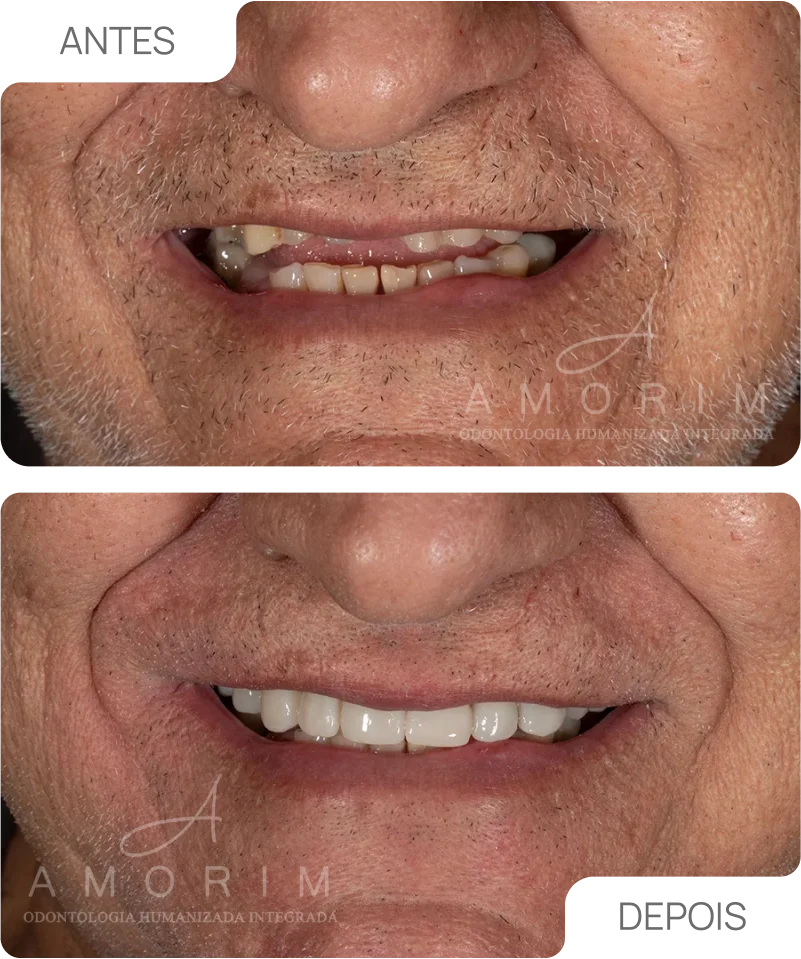

O tratamento de canal é essencial para salvar dentes afetados por cáries profundas, traumas ou infecções, evitando extrações e devolvendo função e estética ao sorriso....